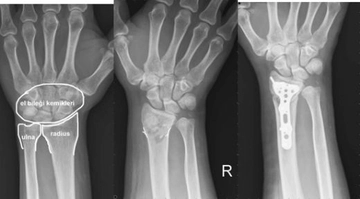

Bu belirtiler acil müdahale gerektiren durumlar arasında yer alır ve dikkatle değerlendirilmelidir. Tanı YöntemleriKalça kırığını teşhis etmek için çeşitli tanı yöntemleri kullanılmaktadır. Bunlar arasında:

Bu yöntemler, kalça kırığının tam yerini ve türünü belirlemek için kritik öneme sahiptir. Tedavi YöntemleriKalça kırığının tedavisi, kırığın tipi, hastanın yaşı ve genel sağlık durumu gibi faktörlere bağlı olarak değişiklik gösterir. Genel olarak kullanılan tedavi yöntemleri şunlardır:

Dirsehan, yaşadığın belirtiler ciddi olabilir. Şiddetli ağrı, yerden kalkamama ve yürümekte zorlanma kalça kırığının belirtileri arasındadır. Kesin bir teşhis için mutlaka bir doktora gitmelisin. Röntgen veya diğer görüntüleme yöntemleri ile durumun netleştirilmesi gerekir. En kısa zamanda bir hastaneye başvurmanı tavsiye ederim. Geçmiş olsun.